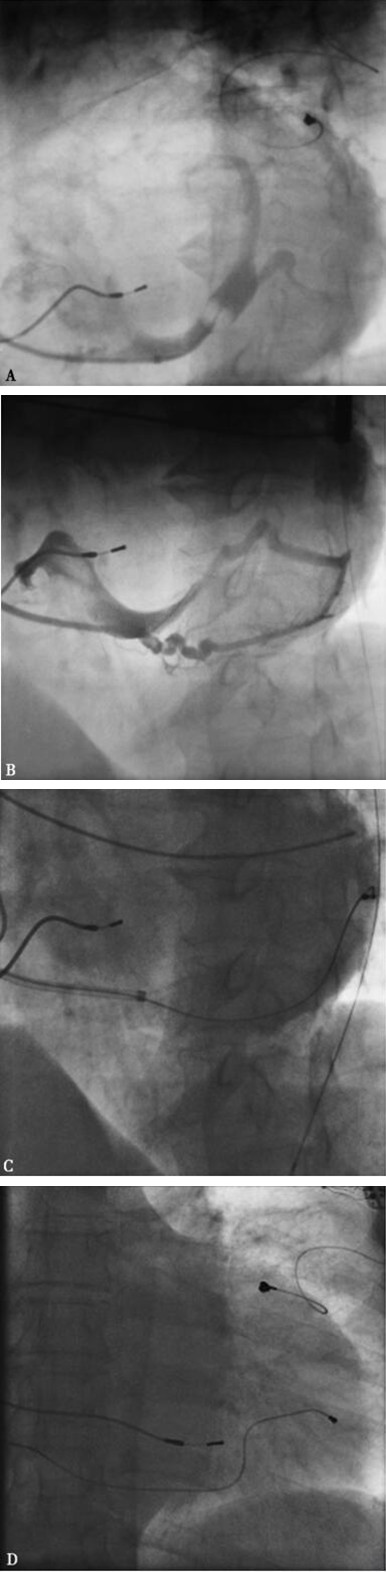

图3-4-16 再次经静脉植入左室电极

A:心中静脉送入PTCA导丝;B:造影显示心后侧静脉与心中静脉形成交通;C:左前斜45°,PTCA导丝从心中静脉逆向送入心后侧静脉,左室电极(4193,Medronic)通过极度弯曲处;D:后前位影像,PTCA导丝从心中静脉逆向送入心后侧静脉,左室电极通过极度弯曲处

进行第2次手术的依据:①患者在术后第3年心力衰竭加重,考虑与左室电极不起搏有关;②患者坚决否定再次心外膜植入左室电极导线的方案;③复习静脉造影片子发现心后侧静脉虽然弯曲,但PTCA导丝可以通过,将1056型(头端为1.67mm,体段为1.86mm,ST. Jude Medical)左室电极换成4193型(头端1.78mm,体段为1.33mm,Medtronic)有成功的希望。在告知患者仍可能有手术不成功的基础上,患者同意再次尝试经静脉植入左室电极,再次签署知情同意书后,于8月5日再次经静脉植入左室电极导线。术中经心脏静脉造影,首先拟把PTCA导丝送至心后侧静脉远端,但反复操作均未成功。尝试从心中静脉送入PTCA导丝成功,并将导丝通过与心后侧静脉的交通送至冠状窦内,沿导丝送入4193电极至心后侧静脉,固定电极在起搏参数最佳的位置(图3-4-16)。术后5天患者出院。